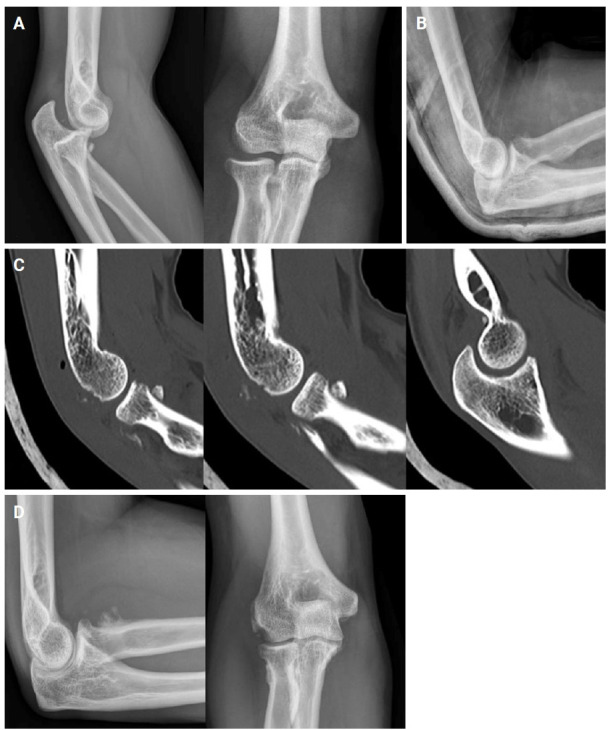

Abstract Image